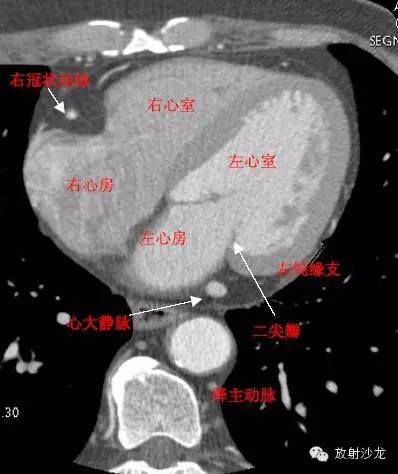

LA -Left Atrium左心房

RA -Right Atrium右心房

LV -Left Ventricle左心室

RV -Right Ventricle右心室

MitralValve二尖瓣

LMB -Left Obtuse Marginal Branch 左边缘支(钝缘支)

RCA -Right Coronary Artery 右冠状动脉

GCV–Great Cardiac Vein心大静脉